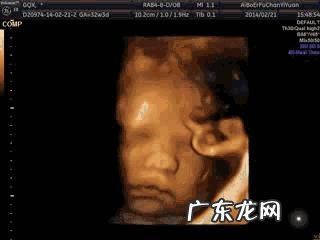

怀孕5个月胎儿的发育情况如下:■胎儿体重:290克左右

■胎儿身长:17厘米(一根香蕉长度)

■感觉器官发育:怀孕5个月,胎儿感觉器官的神经细胞已经开始发育,包括味觉,嗅觉,视觉,触觉还有听觉等,胎儿的味蕾发育已经接近完成;

■分泌胎脂:怀孕5个月,胎儿的皮脂腺也已经开始分泌胎脂,这些白色油腻的胎脂,能为宝宝调节体温起重要作用 。

■羊水量增加:怀孕5个月,胎儿的肾脏已经可以制造尿液,这些尿液将成为羊水的一部分 。胎儿吞咽羊水的能力也是进一步增强;

■怀孕5个月,胎儿的头发,也在迅速生长 。

■胎动增加:怀孕5个月的胎儿,胎动的幅度和力度明显增加 。伸拳踢腿、在子宫内翻滚,吮吸手指,皱眉头,各种搞怪的动作都有,宝宝已经非常调皮了 。